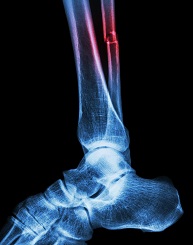

Calf, Ankle & Foot Physical Exam

- Ankle, foot, and toe joint review: